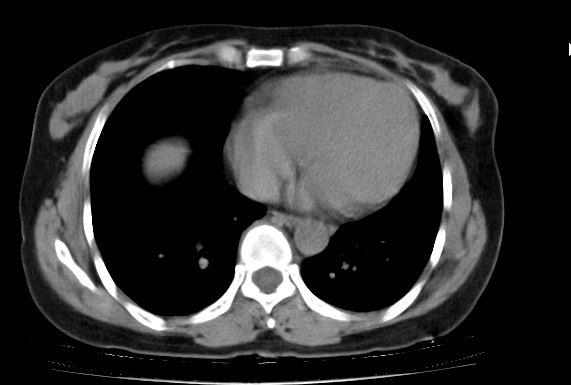

标题: CT25227:背部疼痛伴双侧胸壁痛2月,食欲差。 [打印本页]

标题: CT25227:背部疼痛伴双侧胸壁痛2月,食欲差。

肺结核并胸椎结核?请各位高手指教。

用椎体的条件来扫胸椎呀!考虑1左侧胸膜小结节形成2椎体结核并冷脓肿形成

左肺结核灶,胸椎结核并冷脓肿。

左肺结核灶,胸椎结核并冷脓肿